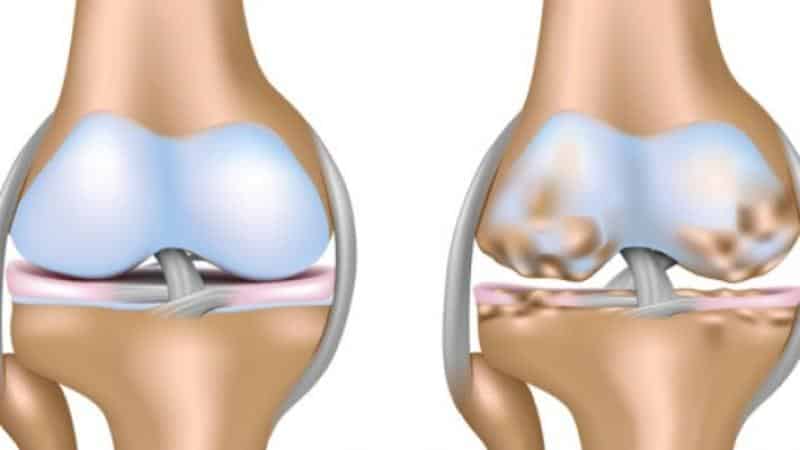

Начало патологического процесса характеризуется незначительными повреждениями гиалиновых хрящей, что в свою очередь приводит к изменениям в окружающих тканях. В результате этого начинает развиваться хроническое поражение синовиальных суставов.

Основой патогенеза является нарушение метаболизма хрящевой ткани, при котором катаболические процессы значительно превышают анаболические.

С прогрессированием болезни в тканях начинают накапливаться соли, что приводит к постепенному деформированию сустава.

- На последних стадиях заболевания наблюдается значительное ограничение подвижности и деформация суставов.